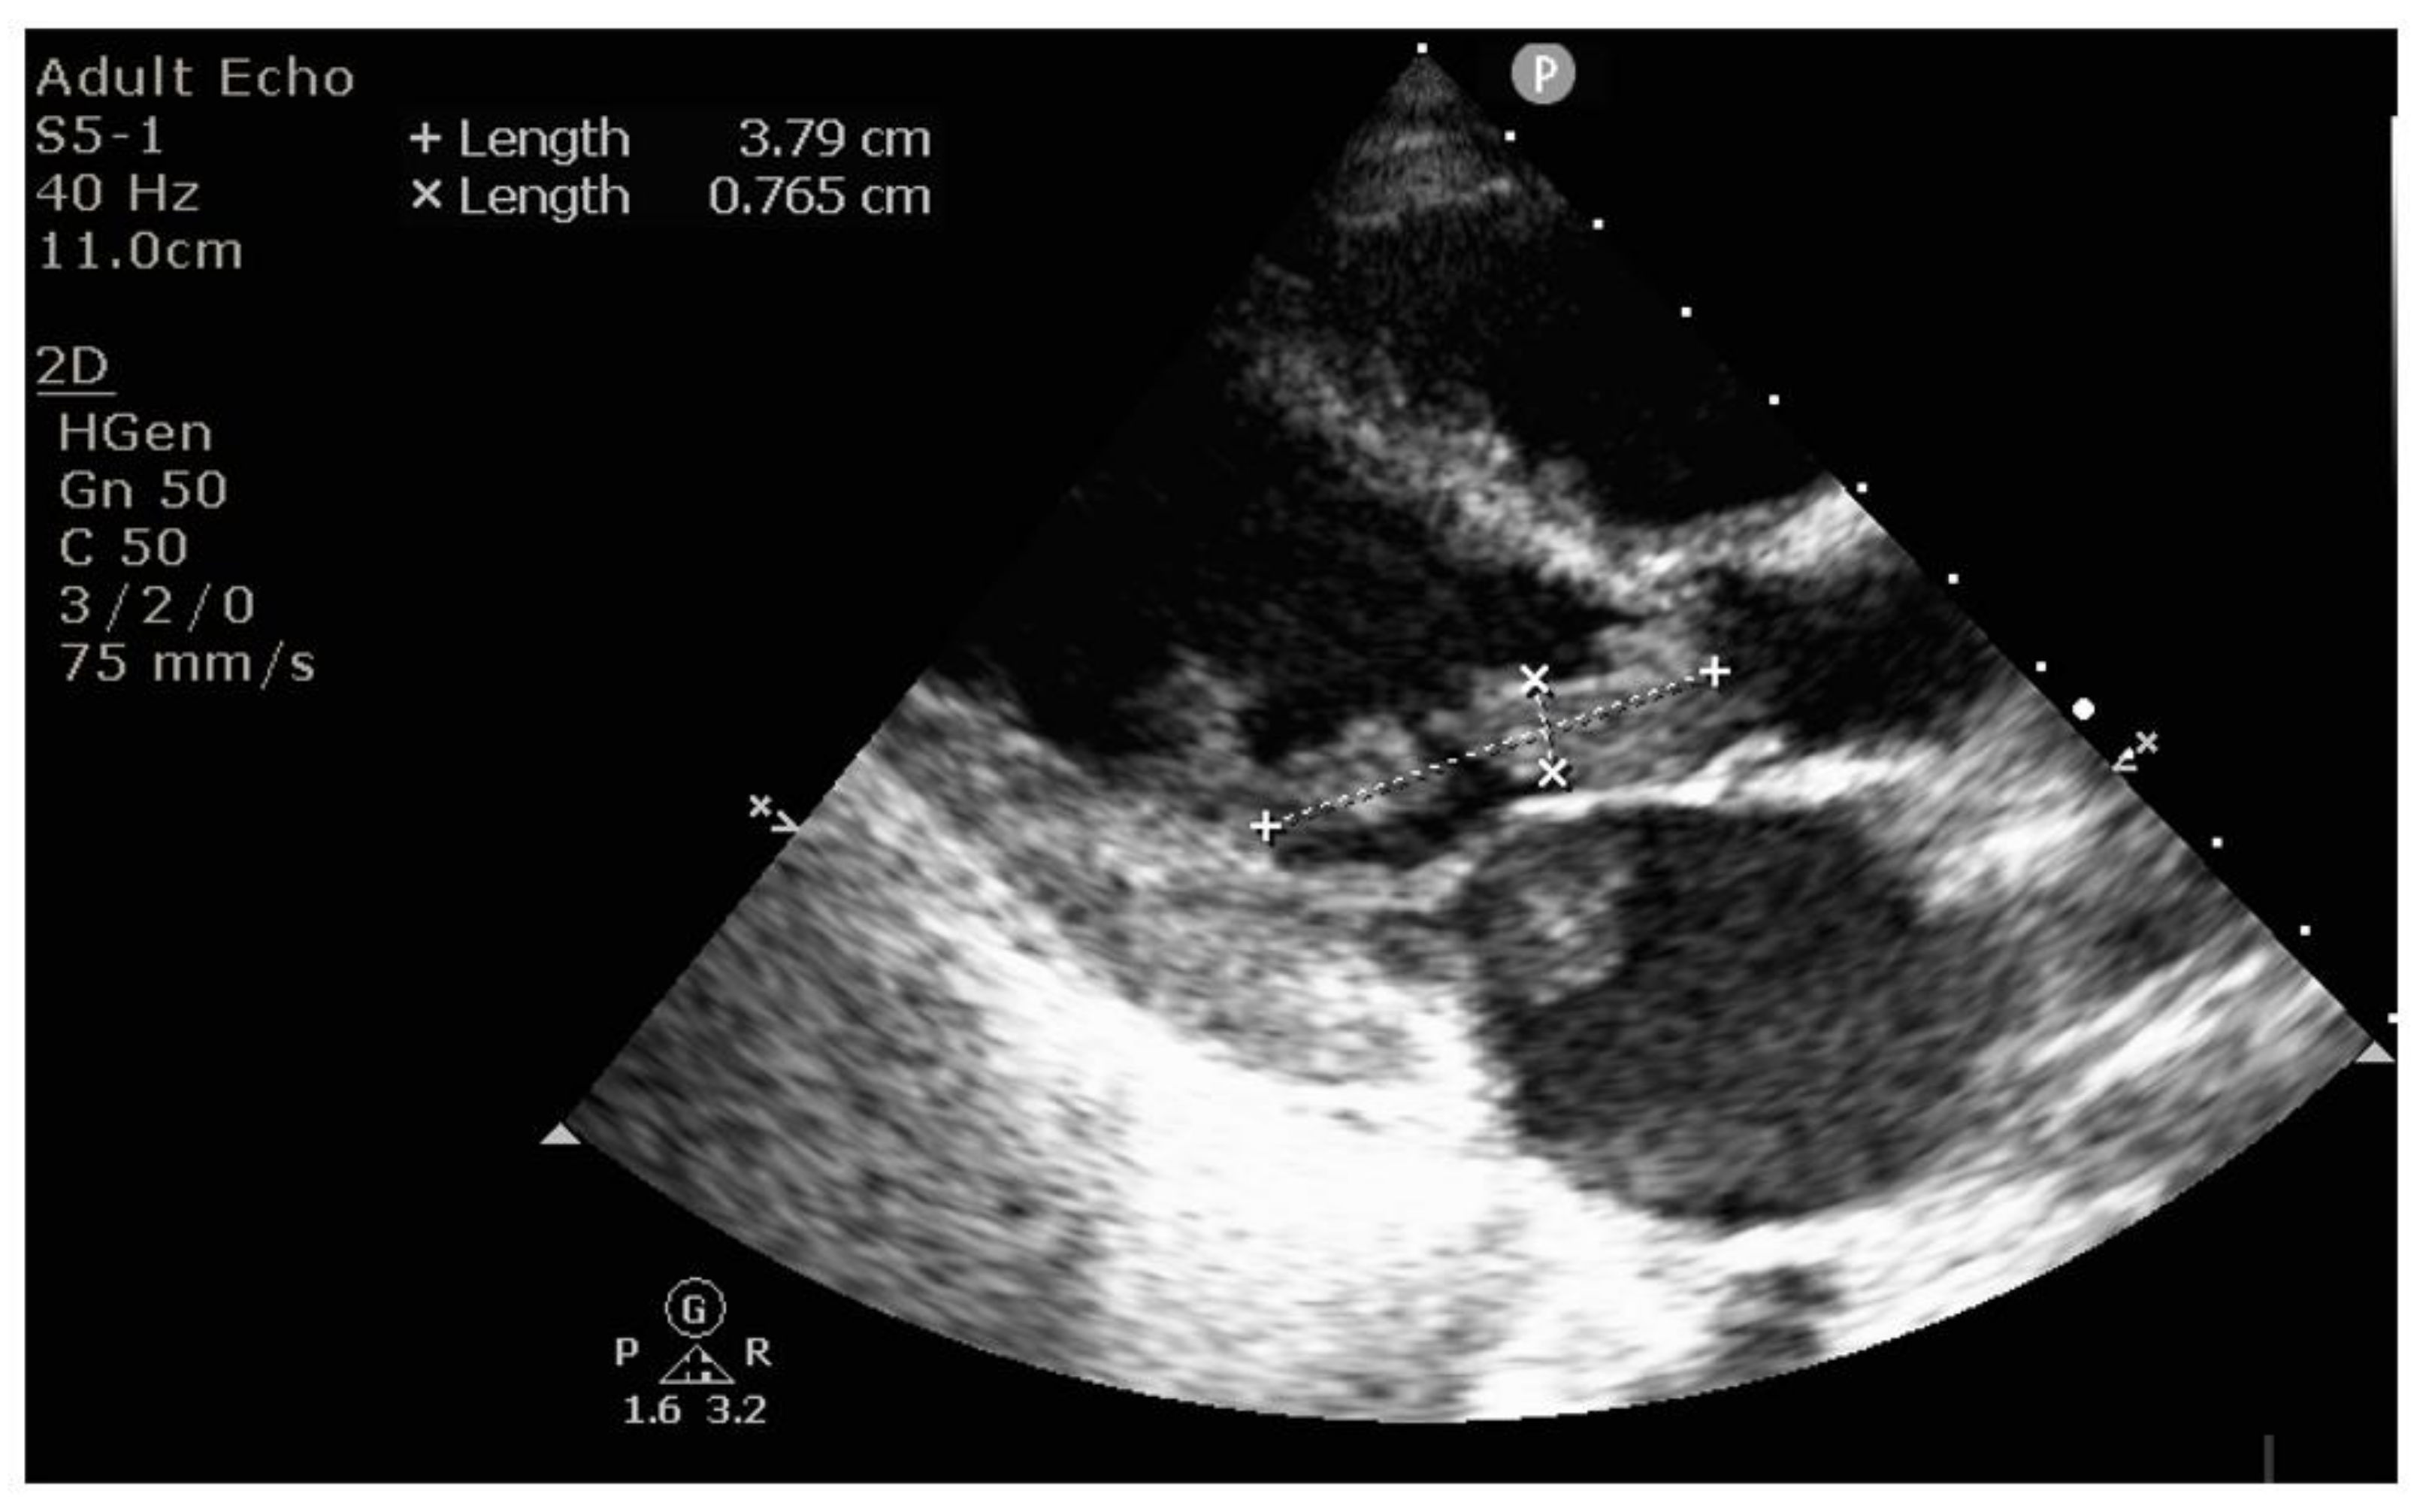

2. Case Report